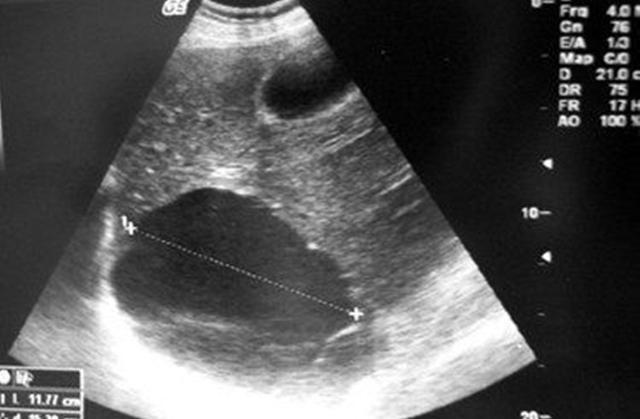

第二种B超单子

1、孕囊是圆形的,生女孩的几率特别的大,如果肚子是茄子或者长形的,生男孩的几率就特别的大。

2、看孕囊的长度,如果长和宽是二倍的关系,那么男孩的几率太大了,如果是差不多等长的,那么生女孩的可能性大。